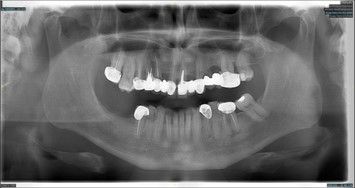

DENTAL IMPLANT SOLUTIONS

FULL ARCH BRIDGE

Five dental implants retaining a fixed upper bridge with individually fabricated zirconia crowns on a precision milled framework with ceramic gum.

FULL ARCH BAR RETAINED

Four dental implants placed in the mandible and maxilla can be linked with a precision milled bar to retain and support an overdenture. This has the advantage of being removable for cleaning and maintenance.

IMPLANT RETAINED DENTURE

Four dental implants in the upper arch with precision attachments can retain a denture that does not need coverage of the palate to retain it. This allows the enjoyment of food taste and temperature to be retained.